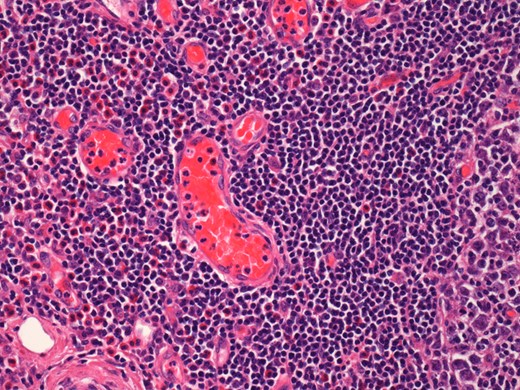

On histological examination the lymph node tissue demonstrated preserved normal architecture. Capsular fibrosis and follicular hyperplasia was noted. The secondary follicles showed polarized germinal centres with tingible body macrophages and well defined mantle zones. The paracortex was expanded by a mixed chronic inflammatory cell infiltrate. Scattered eosinophils were also observed. The parotid parenchyma was mostly replaced by a diffuse lymphoid infiltrate. The residual parotid gland showed lymphoid aggregates in a periductal location. The lymphoid component demonstrated prominent follicular hyperplasia and well developed mantle zones. Parafollicular expansion by an eosinophil-rich mixed inflammatory cell infiltrate was present. Prominent hyalinization of the sinusoidal vessels with thick collagen bundles within the surrounding stroma was also observed. Eosinophil clumps were seen in areas, infiltrating the follicle locally (Figs 5 and 6).

Histological examination of the parotid gland demonstrating eosinophil-rich mixed inflammatory cell infiltrate. Prominent hyalinization of the sinusoidal vessels with thick collagen bundles within the surrounding stroma can be observed (haematoxylin and eosin stain, ×20).